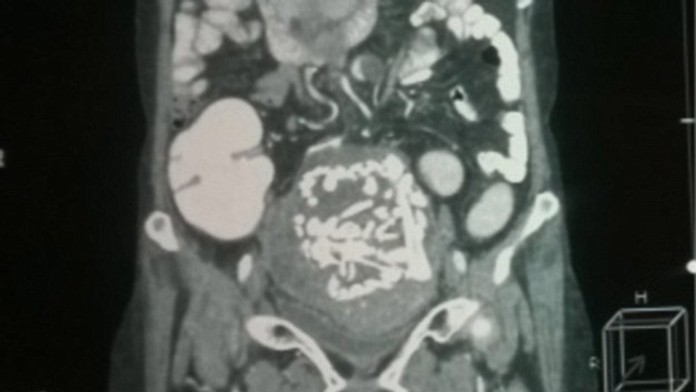

Pacientka sa sťažovala na veľké bolesti brucha. Lekári po vyšetreniach neverili vlastným očiam.

V mestskej nemocnici v Indii mal tím lekárov naozaj unikátny prípad. Obyvateľku Indie, Thakre (60) trápili už dlhšie bolesti brucha. Keď však zašla k lekárovi, nikto neveril vlastným očiam. V jej brušnej dutine našli 36-rokov starú kostru dieťaťa.

Kantabai Gunvant Thakre našli po ultrazvuku v jej brušnej dutine. Zprvu si mysleli, že je to rakovina. Po opakovaných vyšetreniach ich však výsledok vyviedol z miery.

"Po tom, čo pacient podstúpil vyšetrenie magnetickou rezonanciou, lekári usúdili, že ide o kostru dieťata," hovorí Dr. Murtaza Akhtar, vedúci chirurgie v Indickej nemocnici.

"Požiadali sme o podrobnú anamnézu. Samotná pacientka nám neskôr povedal, že v roku 1978 bola tehotná a mala nejaké komplikácie," povedal Dr BS Geda, ktorý viedol tím lekárov.

Operáciu lekári vykonali 14. augusta, trvala štyri hodiny. Podľa lekárov sa pacientka rýchlo zotavuje.